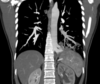

2 anos, masculino

Cisto de duplicação esofágico

Predleção por meninos; diagnosticados na infância

Em geral assintomáticos; podem provocar estridor

Mais comuns no esôfago distal; geralmente não comunicam com a luz do esôfago;

TC: Cisto com densidade de líquido, margens bem definidas que podem realçar com contraste; podem complicar com hemorragia, infecção: nível liquido, espessamento parietal.